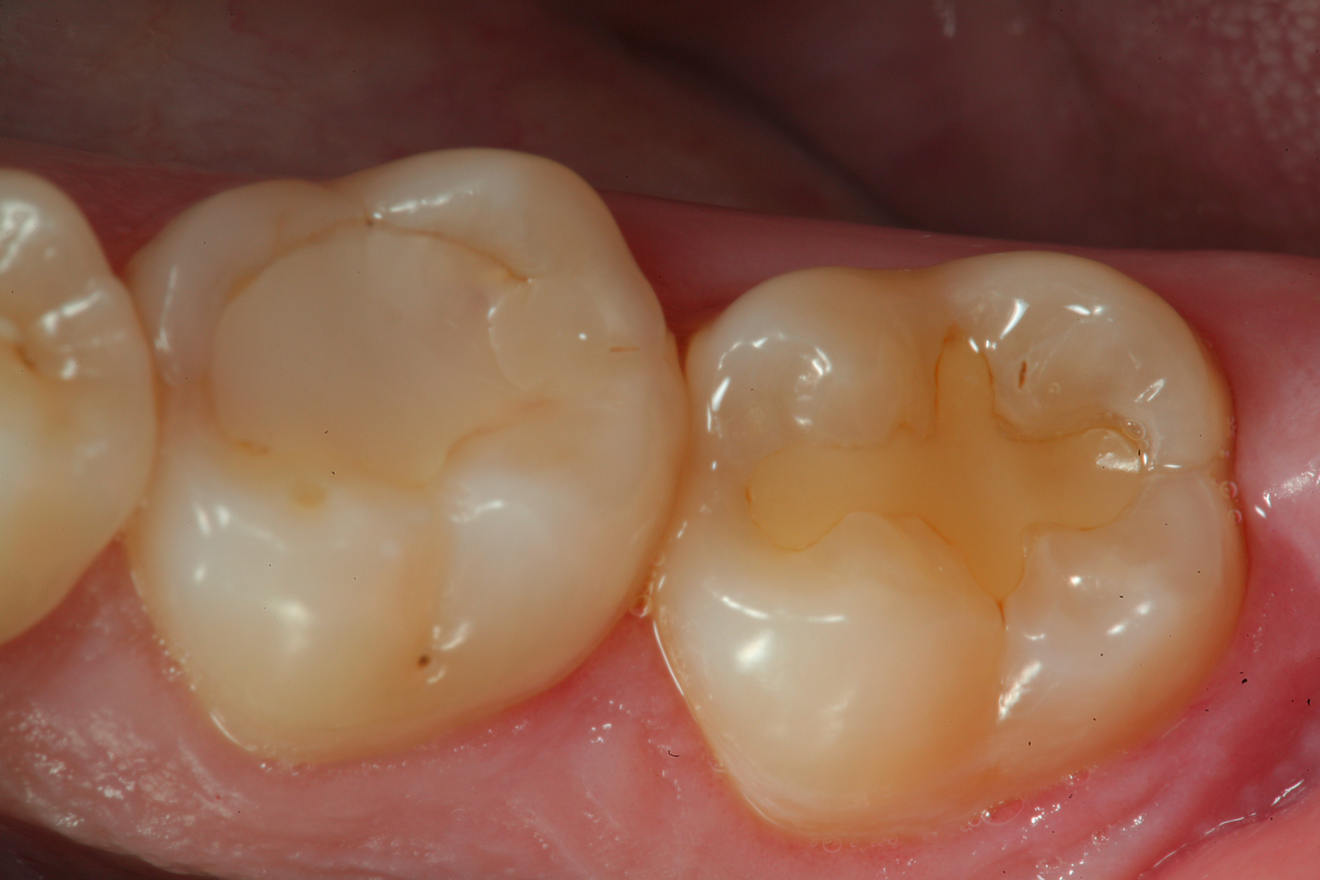

A 32 year-old female patientpresented with old composite restorations in tooth Nos. 18 and 19 that exhibited marginal leakage with potential for recurrent decay (Figure 10).  After excavation, both teeth had deep decay beyond the extent of the restorative material, with tooth No. 19 having a "pinpoint" carious exposure of the pulp chamber (Figure 11).  Figure 12 is a diagrammatic representation of the therapeutics that were used after removal of infected dentin and control of the bleeding from the pulp exposure.  A pulp protectant/liner that is indicated for use on a direct pulp exposure (TheraCal LC, Bisco Dental Products) was placed directly on the exposed area and light cured.  Both preparations were then filled with a bioactive dentin replacement (TheraBase, Bisco Dental Products) to a point just apical to the dentoenamel junction (Figure 13).  Selective etch protocol was then used, etching the enamel (Select Etch HV, Bisco Dental Products) for 15 seconds (Figure 14), then rinsing with water and drying.  Next, a universal bonding agent (All-Bond Universal, Bisco Dental Products) was placed, air thinned, and light cured (Figure 15).  Figure 16 is an occlusal view of the completed restorations.  Both teeth are planned to be followed and radiographed periodically to ensure that the pulps are responding favorably.

Fig 16. An occlusal view of the completed composite restorations on tooth Nos. 18 and 19.

Figure 16